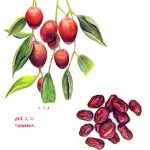

大棗

クロウメモドキ科の棗(なつめ)の果実。